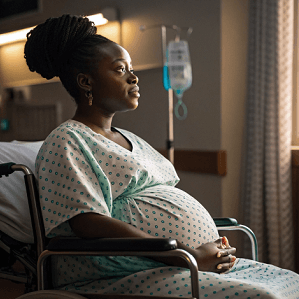

Maternal Mortality

Black Mothers Face Worsening Mortality Gap After Pandemic

Black Maternal Mortality Rate Remains Alarmingly High

Maternal Complications

Black Mothers Face Rising Health Risks, Report Warns